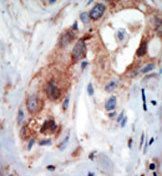

Supportive validation

- Submitted by

- Acris Antibodies GmbH (provider)

- Main image

- Experimental details

- Formalin-fixed and paraffin-embedded human cancer tissue reacted with the primary antibody, which was peroxidase-conjugated to the secondary antibody, followed by AEC staining.